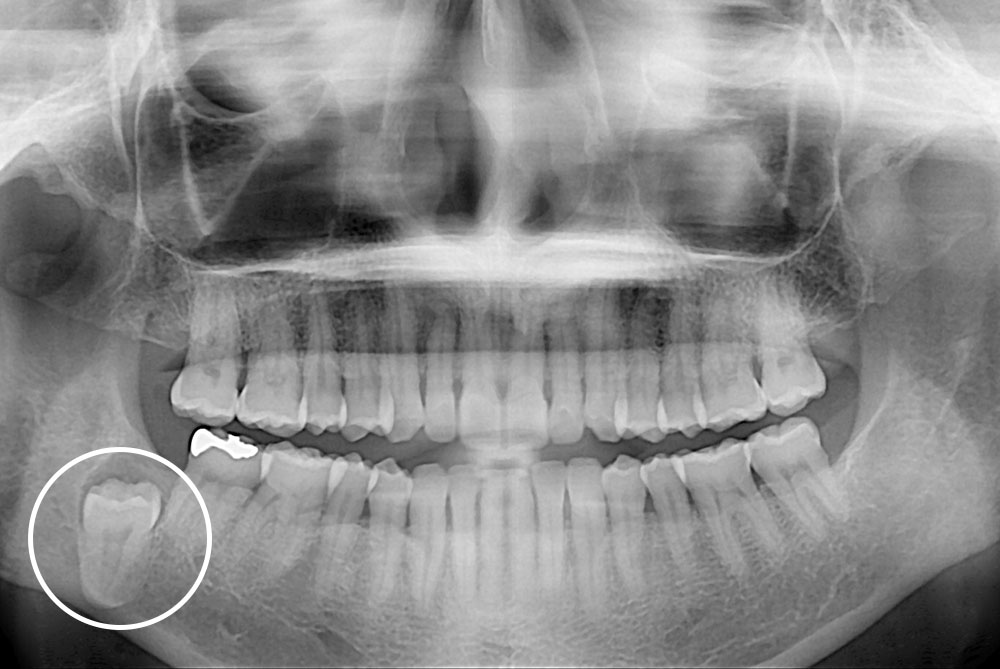

[사랑니] 매복 사랑니 발치

치료후 : 2017-03-15